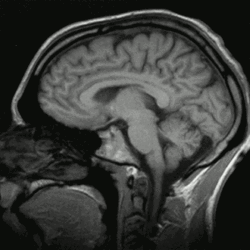

O cérebro humano é o órgão central do sistema nervoso humano e, com a medula espinhal, forma o sistema nervoso central. O encéfalo consiste no cérebro, no tronco cerebral e no cerebelo. O cérebro controla a maioria das atividades do corpo, ao mesmo tempo em que processa, integra e coordena as informações que recebe do sistema sensorial e toma decisões quanto às instruções enviadas ao resto do corpo. O órgão, que está contido e protegido pelos ossos do crânio da cabeça e é a maior parte do encéfalo humano, consiste em dois hemisférios cerebrais. Cada hemisfério possui um núcleo interno composto de matéria branca e uma superfície externa - o córtex cerebral - composto de matéria cinzenta. O córtex tem uma camada externa, o neocórtex e um alocórtex interno. O neocórtex é formado por seis camadas neuronais, enquanto o alocórtex tem três ou quatro. Cada hemisfério é convencionalmente dividido em quatro lobos cerebrais - frontal, temporal, parietal e occipital. O lobo frontal está associado às funções executivas, como autocontrole, planejamento, raciocínio e pensamento abstrato, enquanto o lobo occipital é dedicado à visão. Dentro de cada lobo, áreas corticais estão associadas a funções específicas, como as regiões sensoriais, motoras e de associação. Embora os hemisférios esquerdo e direito sejam bastante semelhantes em forma e função, algumas funções estão associadas especificamente a um lado, como a linguagem à esquerda e a habilidade visual-espacial à direita. Os hemisférios são conectados por tratos nervosos comissurais, sendo o maior o corpo caloso.

O tronco cerebral consiste no mesencéfalo, na ponte e no bulbo raquidiano. O cerebelo está conectado ao tronco cerebral por três pares de tratos nervosos chamados pedúnculos cerebelares. Dentro do cérebro está o sistema ventricular, que consiste em quatro ventrículos interconectados nos quais o líquido cefalorraquidiano é produzido e circulado. Abaixo do córtex cerebral existem várias estruturas importantes, incluindo o tálamo, o epitálamo, a glândula pineal, o hipotálamo, a glândula pituitária e o subtálamo; as estruturas límbicas, incluindo a amígdala e o hipocampo; o claustro, os vários núcleos dos gânglios da base; as estruturas basais do prosencéfalo e os três órgãos circunventriculares. As células do cérebro incluem neurônios e gliocitos. Existem mais de 86 bilhões de neurônios no cérebro e um número mais ou menos igual de outras células. A atividade cerebral é possibilitada pelas interconexões de neurônios e sua liberação de neurotransmissores em resposta aos impulsos nervosos. Os neurônios se conectam para formar caminhos neurais, circuitos neurais e sistemas de rede elaborados. Todo o circuito é impulsionado pelo processo de neurotransmissão.

Córtex cerebral

No cérebro há uma distinção visível entre a chamada massa cinzenta e a massa branca, constituída pelas fibras (axónios) que interligam os neurónios. A substância cinzenta do cérebro, o córtex cerebral, é constituído de corpos celulares de dois tipos de células: as células de Glia - também chamadas de neuróglias - e os neurônios. O córtex cerebral humano é um tecido fino (como uma membrana) que tem uma espessura entre 1 e 4 mm e uma estrutura laminar formada por 6 camadas distintas de diferentes tipos de corpos celulares de neurônios. Perpendicularmente às camadas, existem grandes neurônios chamados neurônios piramidais que ligam as várias camadas entre si e representam cerca de 85% dos neurônios no córtex. Os neurônios piramidais estão interligados uns aos outros através de ligações excitatórias e pensa-se que a sua rede é o "esqueleto" da organização cortical. Podem receber entradas de milhares de outros neurônios e podem transmitir sinais a distâncias da ordem dos centímetros e atravessando várias camadas do córtex. Os estudos realizados indicam que cada célula piramidal está ligada a quase tantas outras células piramidais quantas as suas sinapses (cerca de 4 mil); o que implica que nenhum neurônio está a mais de um número pequeno de sinapses de distância de qualquer outro neurônio no córtex.

Embora até há poucos anos se pensasse que a função das células de Glia é essencialmente a de nutrir, isolar e proteger os neurônios, estudos mais recentes sugerem que os astrócitos podem ser tão críticos para certas funções corticais quanto os neurônios. As diferentes partes do córtex cerebral são divididas em quatro áreas chamadas de lobos cerebrais, tendo cada uma funções diferenciadas e especializadas. Os lobos cerebrais são designados pelos nomes dos ossos cranianos nas suas proximidades e que os recobrem. O lobo frontal fica localizado na região da testa; o lobo occipital, na região da nuca; o lobo parietal, na parte superior central da cabeça; e os lobos temporais, nas regiões laterais da cabeça, por cima das orelhas.